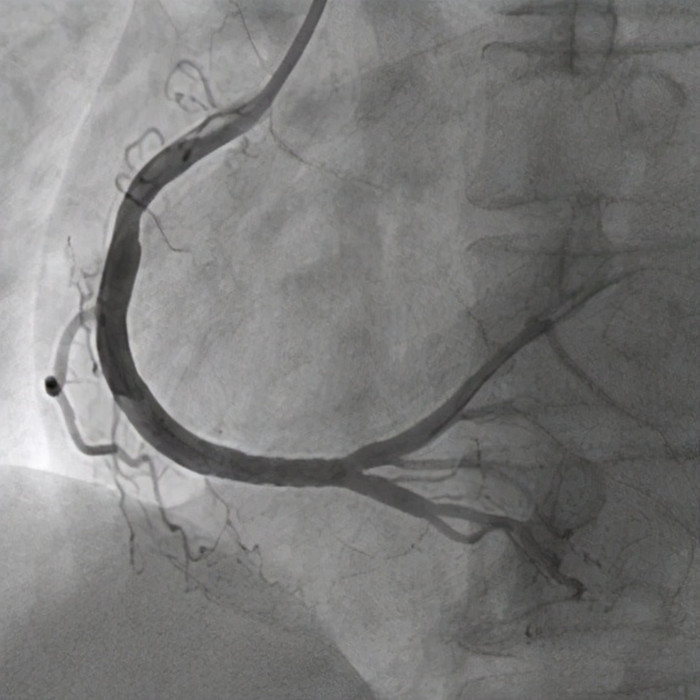

孙先生很顺利地被送入导管室 , 不到10分钟就做完了心脏造影 , 左主干根部完全堵塞 , 还没来得及做右侧血管造影 , 准备先植入IABP , 辅助心脏循环 。 这时候患者的心脏停止了跳动 , 导管室医护人员立即胸外按压心肺复苏 。 可是这种左主干闭塞的心肌梗死 , 一旦心脏停跳 , 可以说神仙也很难救活!

心脏两根血管完全堵塞